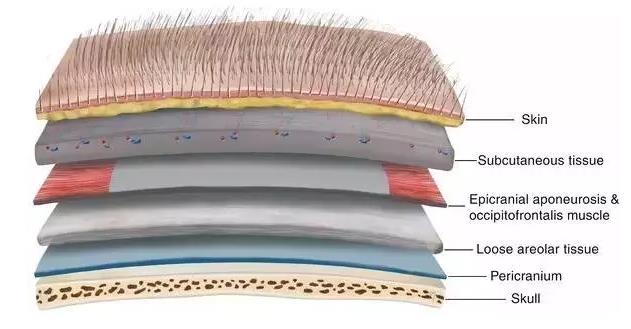

我們從外往里看吧。生物學有時似乎非常讓人滿意,比如你的頭上有一個真正的俄羅斯套娃。

你有頭發,然后是頭皮,你認為下面就是你的頭骨了——但實際上頭骨之上還有19樣東西。

你的頭骨下面,又是一大堆東西,之后才是你的大腦:

我們從外往里看吧。生物學有時似乎非常讓人滿意,比如你的頭上有一個真正的俄羅斯套娃。

你有頭發,然后是頭皮,你認為下面就是你的頭骨了——但實際上頭骨之上還有19樣東西。

你的頭骨下面,又是一大堆東西,之后才是你的大腦: